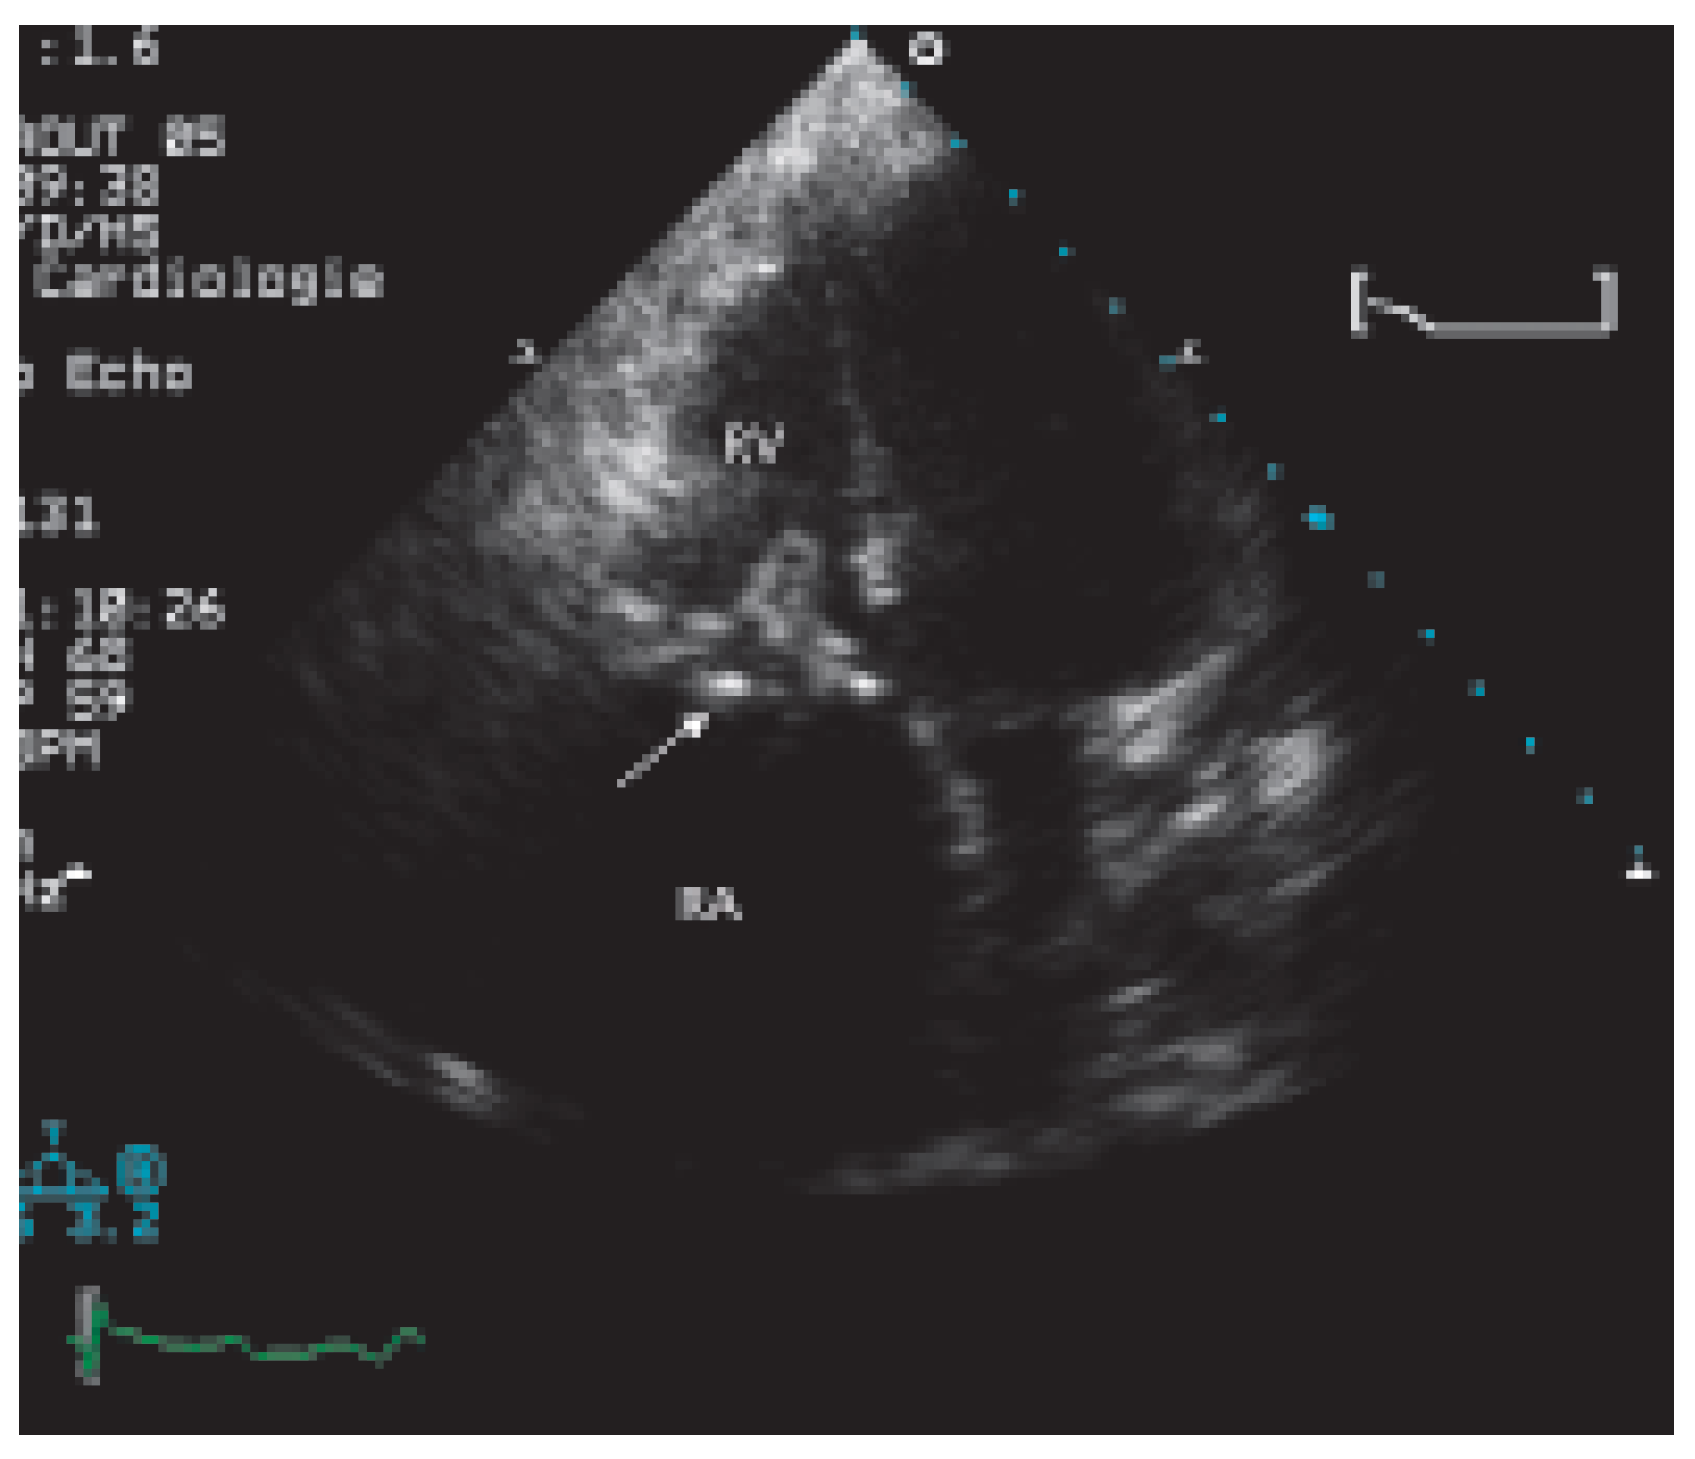

Case report